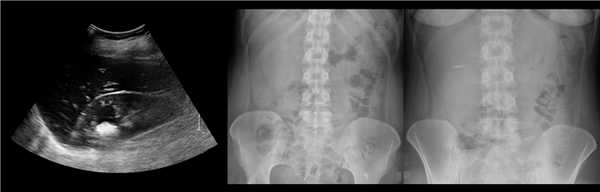

Рисунок. У новорожденного на УЗИ почек определяется гидронефроз (1) и расширенный мочеточник (2) справа. В мочевом пузыре двустороннее уретероцеле (3). При исследовании левой почки структурных изменений не выявлено.

Рисунок. На УЗИ определяется удвоенная чашечно-лоханочная система, расширена лоханка верхнего сегмента (1) и мочеточник на всем протяжение (2, 3), в мочевом пузыре уретроцеле (4). Полное или неполное удвоение чашечно-лоханочной системы возможно увидеть с помощью КТ-урографии.

Рисунок. КТ-урография (1) показывает неполное удвоение ЧЛС слева: два мочеточника соединяются на входе в таз и единым мочеточником вступают в мочевой пузырь; внутрипузырная часть мочеточника расширена (красная стрелка) — уретероцеле. Уретероцеле хорошо видно на рентгенограммах (2) при экскреторной урографии: правый мочеточник расширен на всем протяжении, дистальный отдел кистозно расширен — «голова кобры».